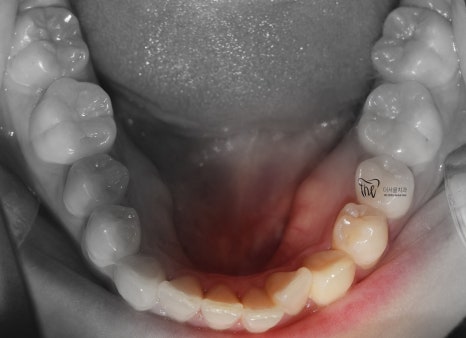

먼저, 임상 사진 5장을 보여드립니다.

그냥 겉으로 봤을 때는 단순 치아들의 불규칙성

때문에 치과에 내원을 하신 것으로 볼 수 있습니다.

그러나, 좌측에서 바라봤을 때는 어금니들이

부정교합을 띄고 있는 것을 볼 수 있습니다.

즉, 거꾸로 물리는 반대교합의 양상을 보여주고

있고 이런 증세 때문에 턱관절의 통증까지도

같이 느끼고 있는 채로 내원을 하셨습니다.